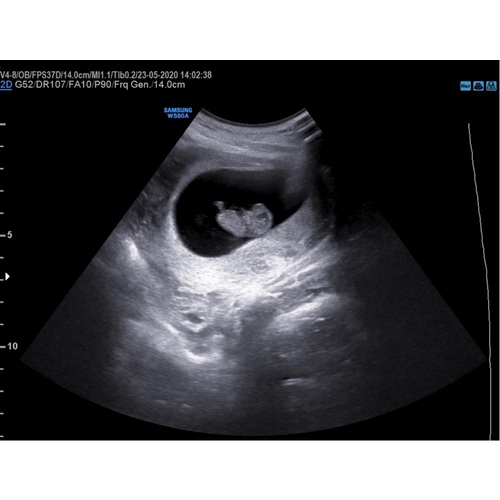

Vandaag een pretecho ingepland als verrassing voor mijn vriend omdat hij niet mee mocht naar de gynaecoloog en het zag er echt heel goed uit. Natuurlijk zit de lege vruchtzak er nog steeds wat ik persoonlijk heel confronterend vind maar verder wel een heel beweeglijke baby. Ik ben ondertussen 10 weken zwanger.